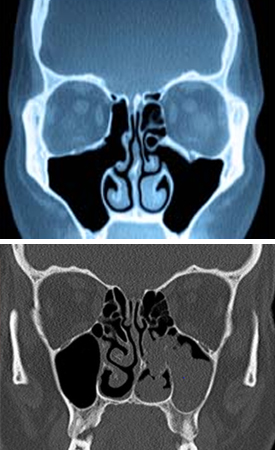

PREVENCIJA, DIJAGNOSTIKA I LIJEČENJE BOLESTI NOSA I PARANAZALNIH SINUSA

• akutne, recidivirajuće i kronične upale nosa i paranazalnih sinusa

• nosne polipoze

• vazomotorne nealergijske i alergijske rinopatije

• endoskopija nosa, paranazalnih sinusa i nazofarinksa